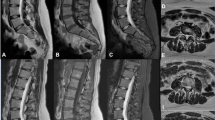

Thirty-five patients (mean age 58 ± 19, 26 female) were evaluated. 3D DLRecon demonstrated statistically significant higher median image quality score (2.0/2) when compared to SOC 3D (1.0/2, p < 0.001), 2D axial (1.0/2, p < 0.001), and 2D sagittal sequences (1.0/2, p value < 0.001). κ ranges (and 95% CI) for foraminal stenosis were 0.55–0.76 (0.32–0.86) for 3D DLRecon, 0.56–0.73 (0.35–0.84) for SOC 3D, and 0.58–0.71 (0.33–0.84) for 2D. Mean κ (and 95% CI) for central stenosis at L4-5 were 0.98 (0.96–0.99), 0.97 (0.95–0.99), and 0.98 (0.96–0.99) for 3D DLRecon, 3D SOC and 2D, respectively.